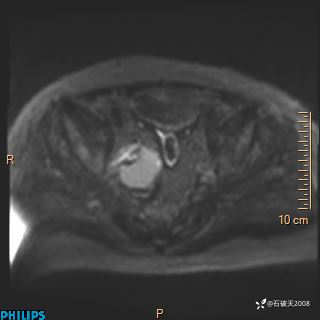

2023年3月份MRI影像

增强轴位